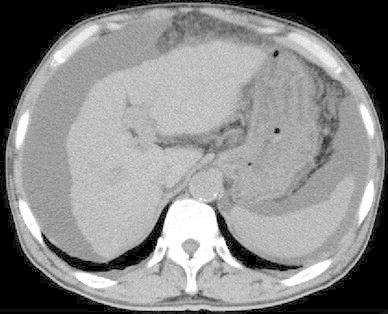

Tolvaptan is a new drug used for treating ascites induced by liver cirrhosis, and it is covered by health insurance in Japan. In the present report, we describe the case of a 74-year-old man with type C liver cirrhosis and refractory ascites. He was receiving furosemide and spironolactone daily, but still required repeat puncture for ascites removal. Administration of tolvaptan (3.75 mg/day) was started in addition to his existing medications, and was subsequently increased to 7.5 mg/day. However, after 2 months, the ascites again exacerbated. Nevertheless, after we discontinued the administration of furosemide, the tolvaptan became effective. This may be because furosemide administration decreases urine osmolality, resulting in a non-response to tolvaptan.

托伐普坦是一种用于治疗肝硬化引起的腹水的新药,在日本已被纳入医保。在本报告中,我们描述了一名74岁丙型肝硬化伴难治性腹水男性患者的病例。他每天接受呋塞米和螺内酯治疗,但仍需反复穿刺抽腹水。在其现有药物治疗基础上开始给予托伐普坦(3.75毫克/天),随后增加至7.5毫克/天。然而,2个月后,腹水再次加重。尽管如此,在我们停用呋塞米后,托伐普坦开始起效。这可能是因为使用呋塞米会降低尿渗透压,导致对托伐普坦无反应。